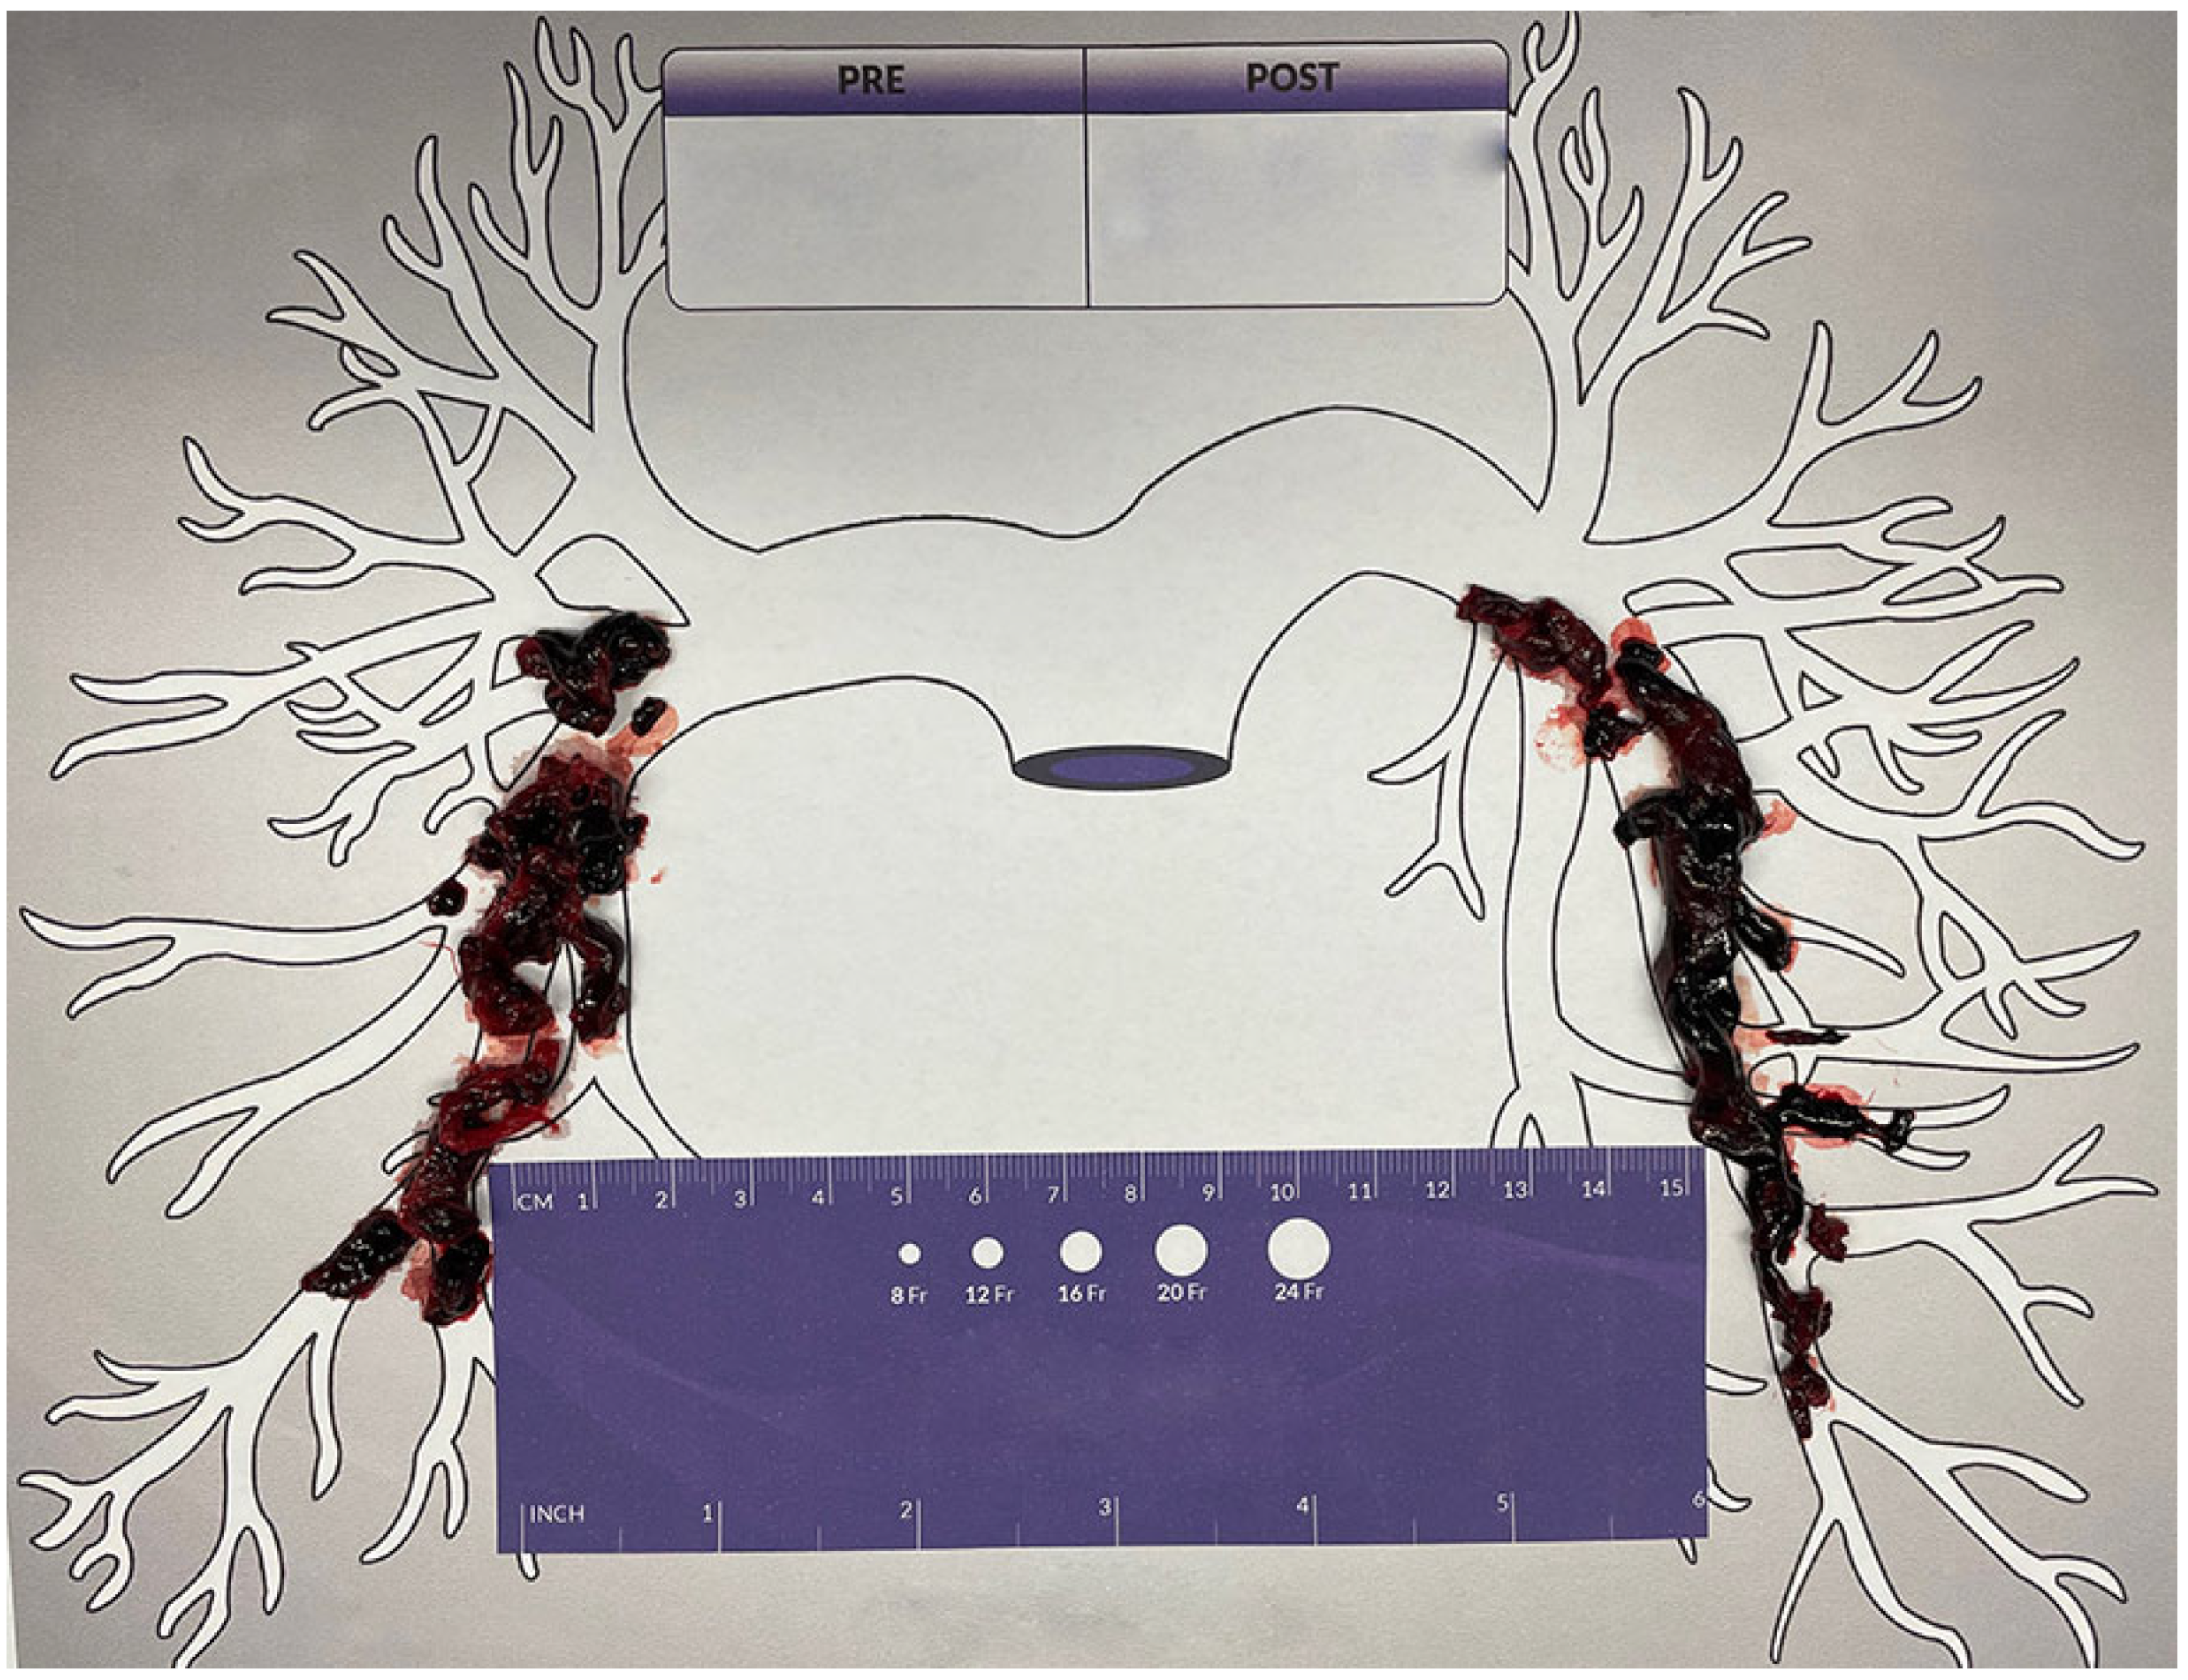

2. Case Report

4. Autotransfusion Procedure